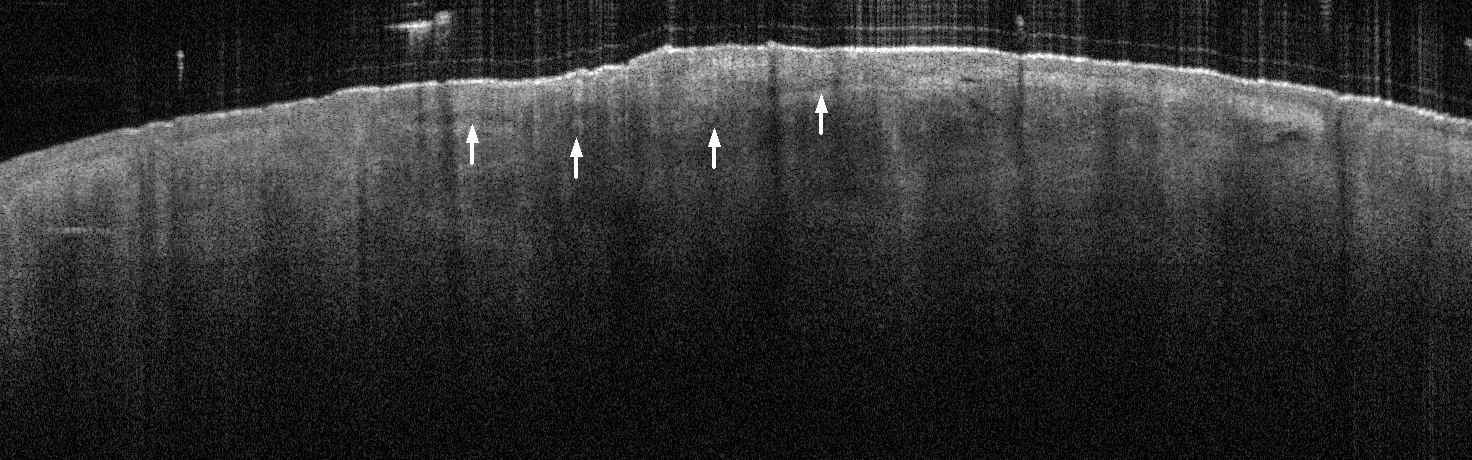

VA35: Left Temple, Actinic Keratosis, Hypertrophic

- White arrows indicate return to dermal collagen texture and reflectivity

VA35: Left Temple, Adjacent, Normal